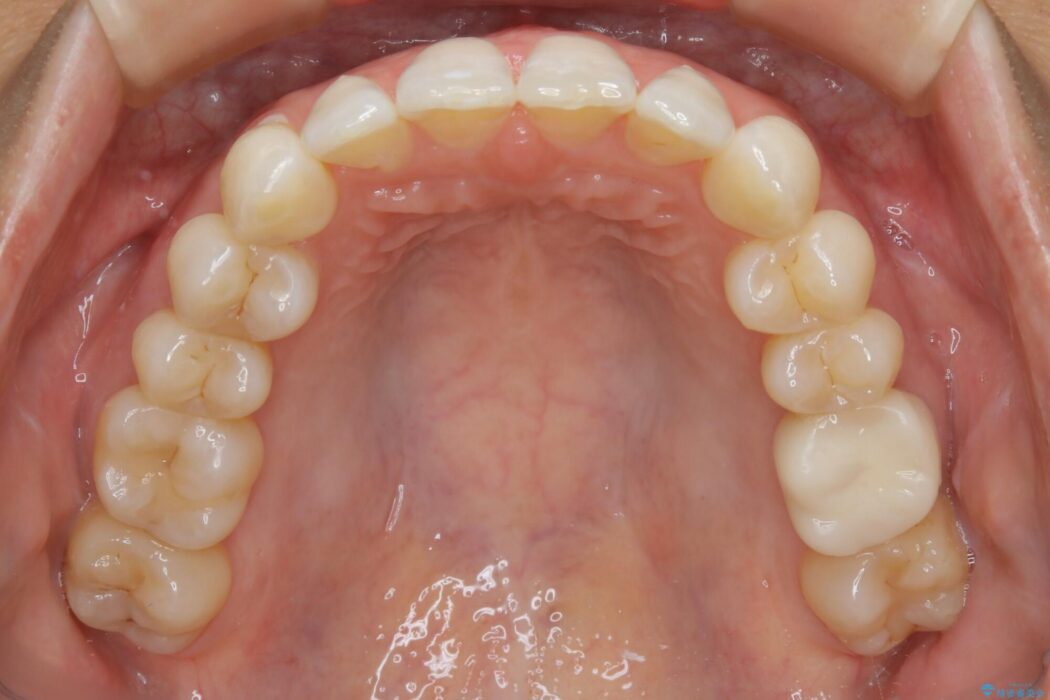

悪くなっている歯の放置はできないと判断しましたので、患者様と様々な治療プランを相談した上で、最終的に該当の歯は抜歯をして噛み合わせを改善し、その後インビザラインでの矯正治療を行うこととしました。

噛み合わせも改善され、一番最初の目的であった歯列もきれいに整いご満足いただけました。